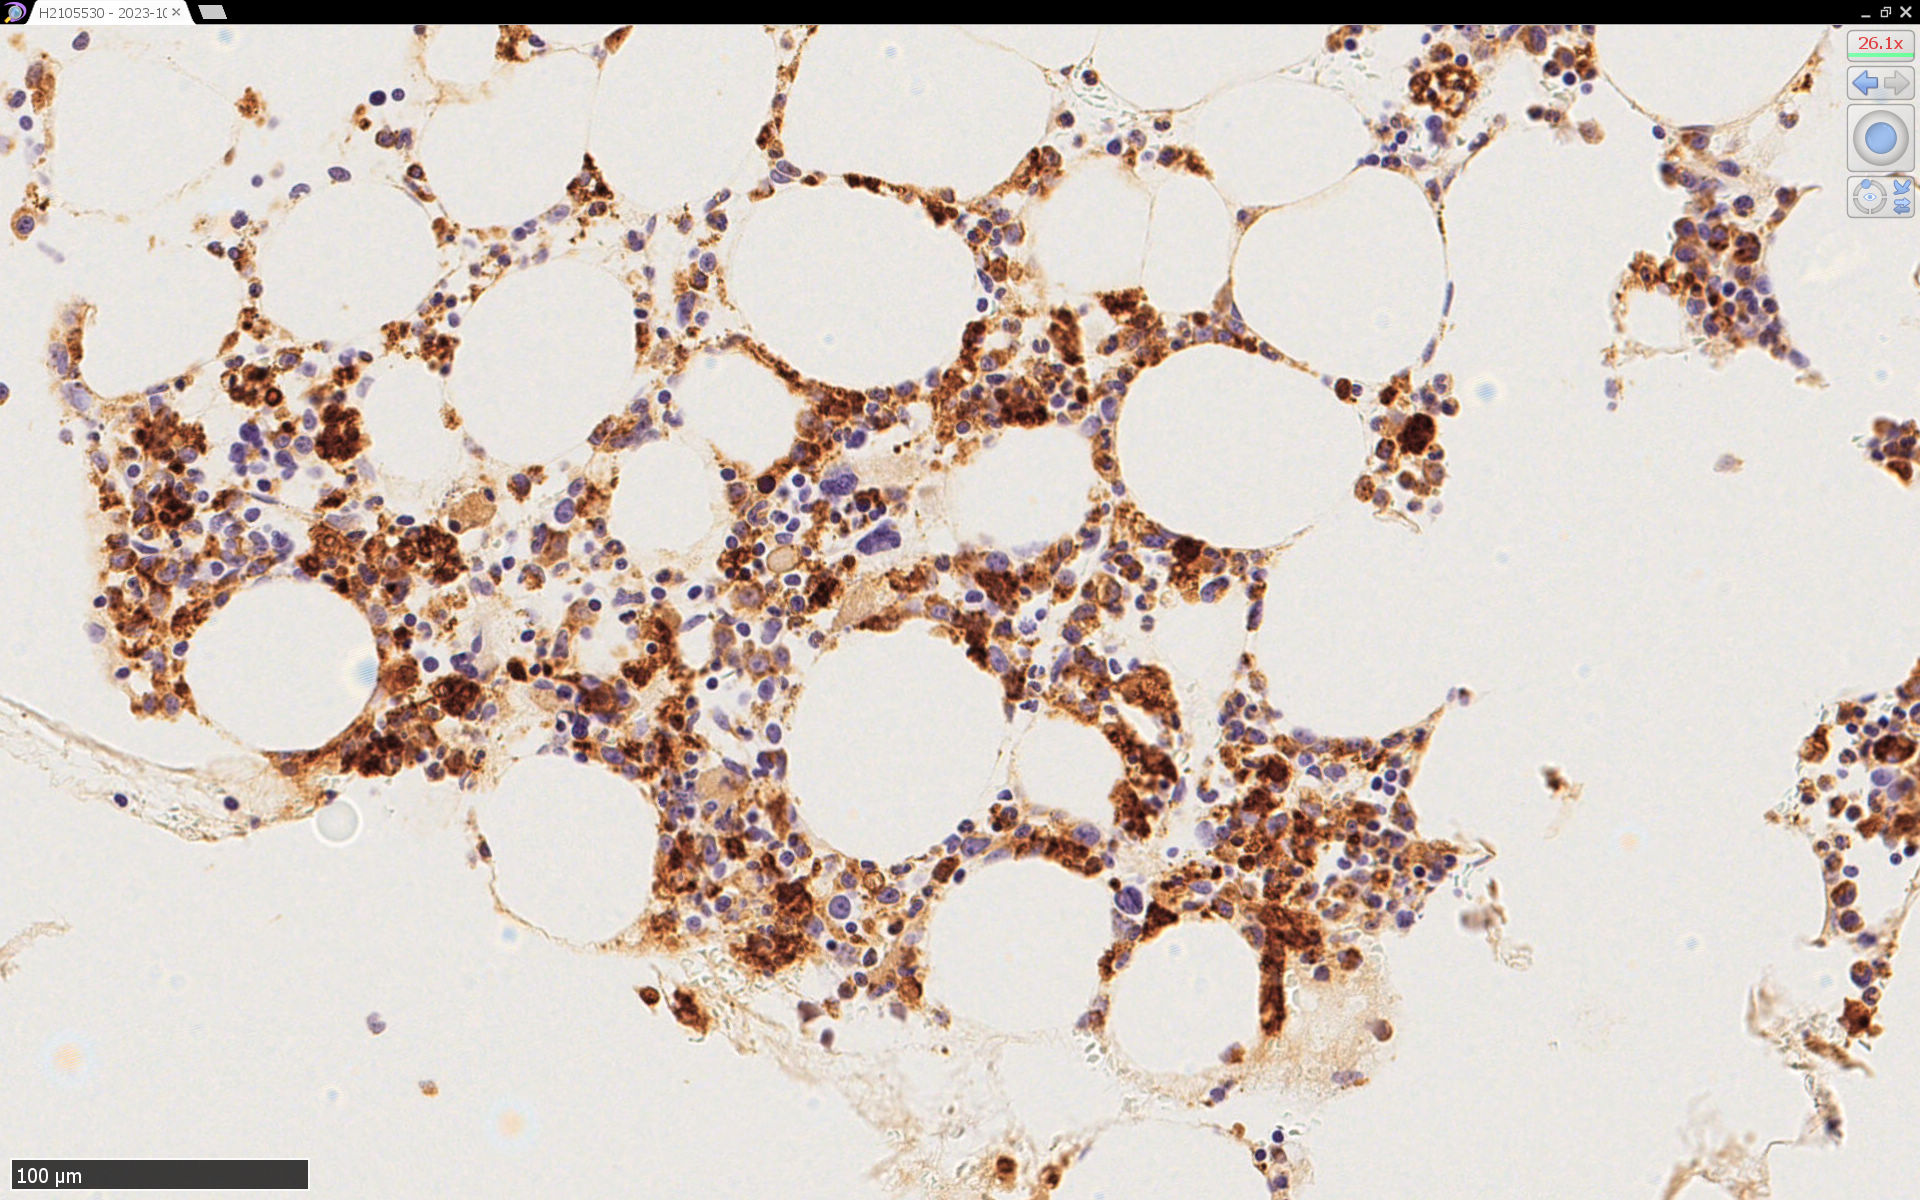

SFTSの骨髄病理所見

症例の報告, 骨髄病理所見--IWT case

Bone marrow smearの所見

異常な巨核球が出現する.

hemophagocytosis 血球貪食像

巨大血小板